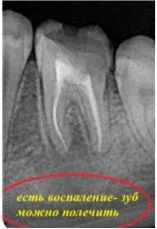

Давайте сравним снимки зубов, сделанные при помощи визиографа (слева), и при помощи компьютерной томографии (справа).

Как говорится, ощутите разницу. КТ - гораздо более точная и своевременная диагностика.